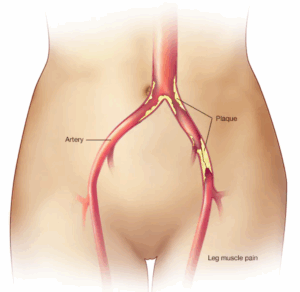

Peripheral artery disease

Peripheral artery disease (PAD) is a common condition in which narrowed arteries reduce blood flow to the arms or legs.